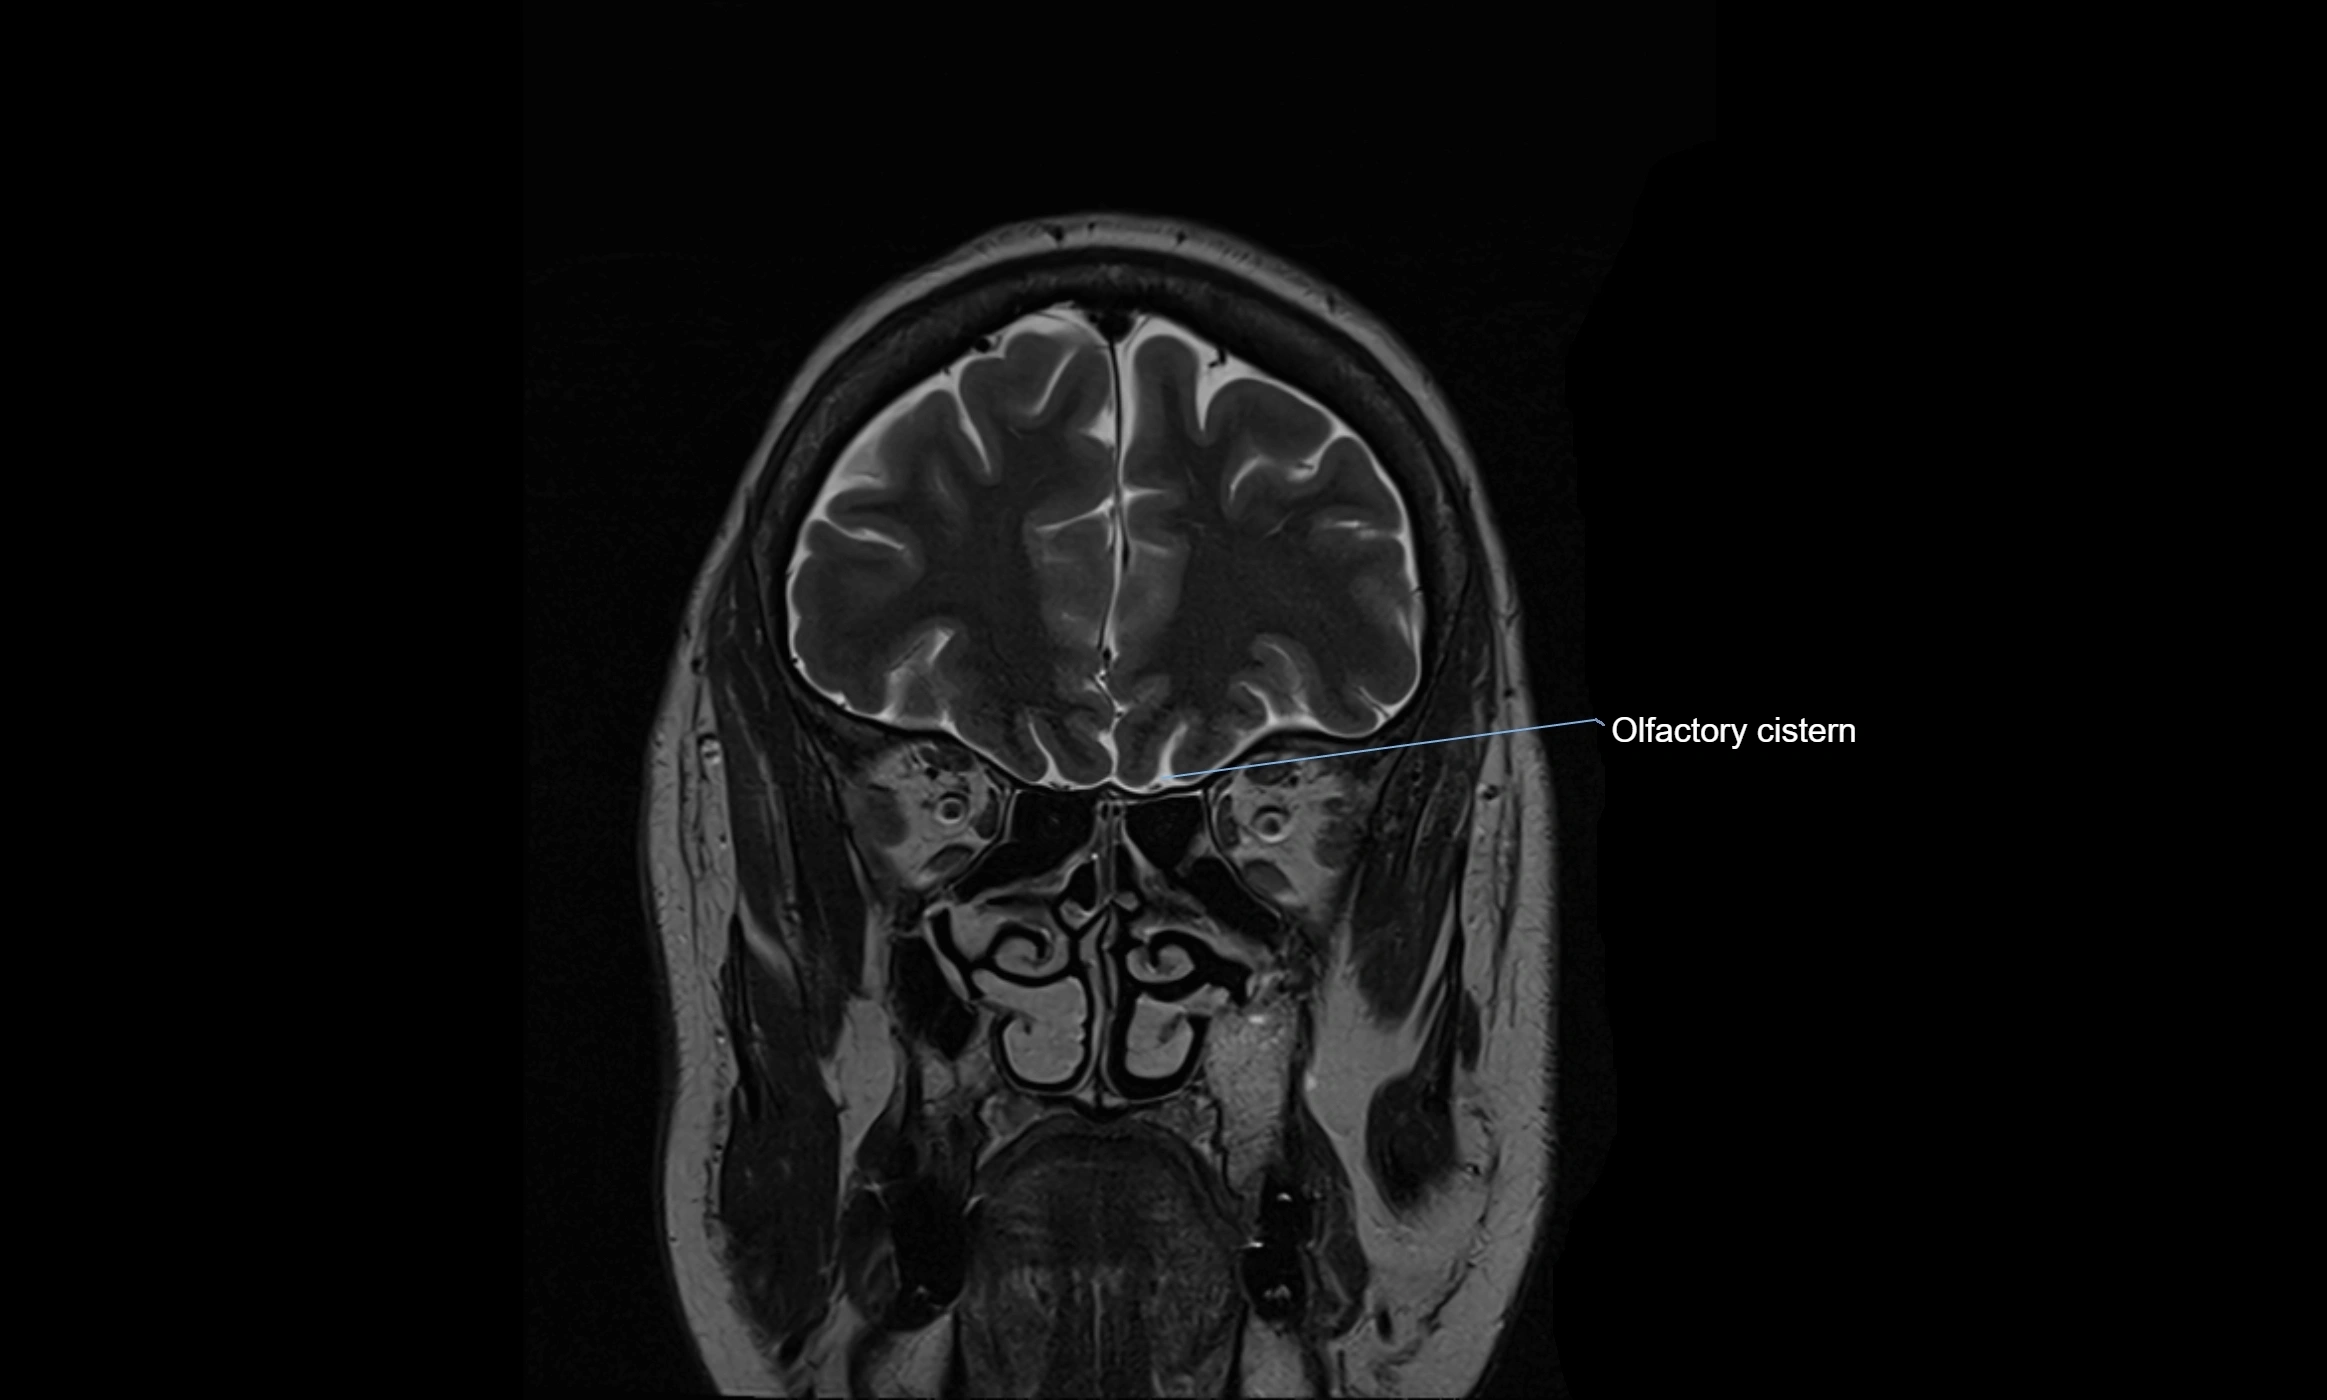

image